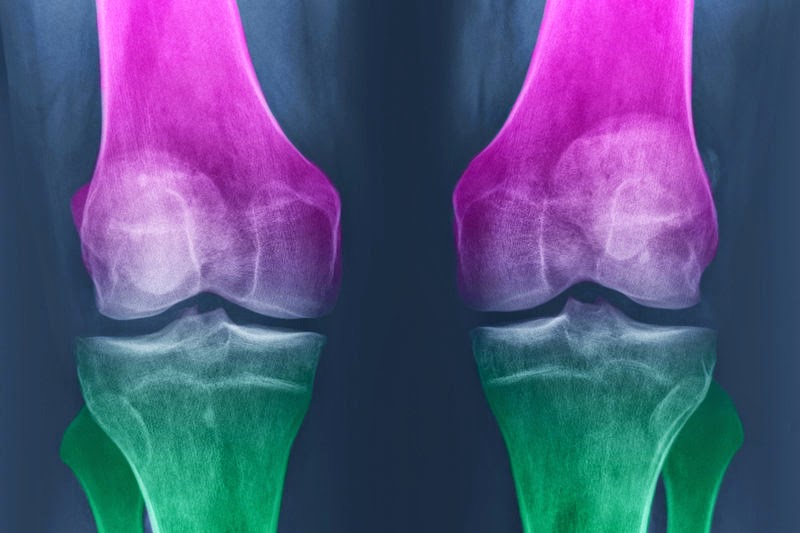

Η αρθρίτιδα προκαλεί πόνο, πρήξιμο και δυσκαμψία στις αρθρώσεις και φθορές στον χόνδρο, με την πάροδο του χρόνου. Έτσι, η αρχική σκέψη ήταν οτι ίσως η χορήγηση γλυκοζαμίνης και χονδροϊτίνης μπορεί να βοηθήσει στη διατήρηση και ακόμη και στην αποκατάσταση της φθοράς.

“Αλλά τα ευρήματα από στην υπάρχουσα μελέτη ήταν πεντακάθαρα”, λέει ο Dr David Felson, ρευματολόγος από την Ιατρική Σχολή της Βοστώνης. “Δεν υπήρχε απολύτως κανένα όφελος για τους περισσότερους ασθενείς που έλαβαν τα συμπληρώματα σε σύγκριση με το εικονικό φάρμακο, που σημαίνει ότι στην ανακούφιση του πόνου τα συμπληρώματα δεν έκαναν τίποτε περισσότερο από ότι αυτό. Τα συμπληρώματα διατροφής δεν επηρέασαν τη δομή της άρθρωσης (όπως βρέθηκε μετά από ακτινογραφίες) και δεν προκάλεσαν καμία καθυστέρηση στην εξέλιξη της νόσου, σε σύγκριση με το εικονικό φάρμακο. Ουσιαστικά δεν είχαν καμία επίδραση.”